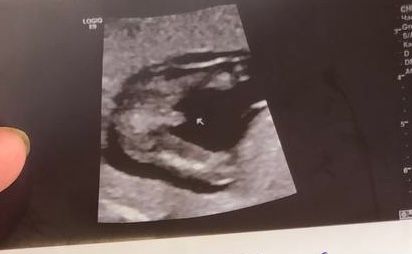

Little Koldynia, вообще нет,мне на первом ,втором говорили мальчик.Увидели девочку только на 3 скрининге.Вот фото 1,2 скрининга.А родила девочку по итогу ))) Изображение Изображение

27.10.2024

Весна, внизу это первый,а вверху второй.Да девочка родилась )

29.10.2024